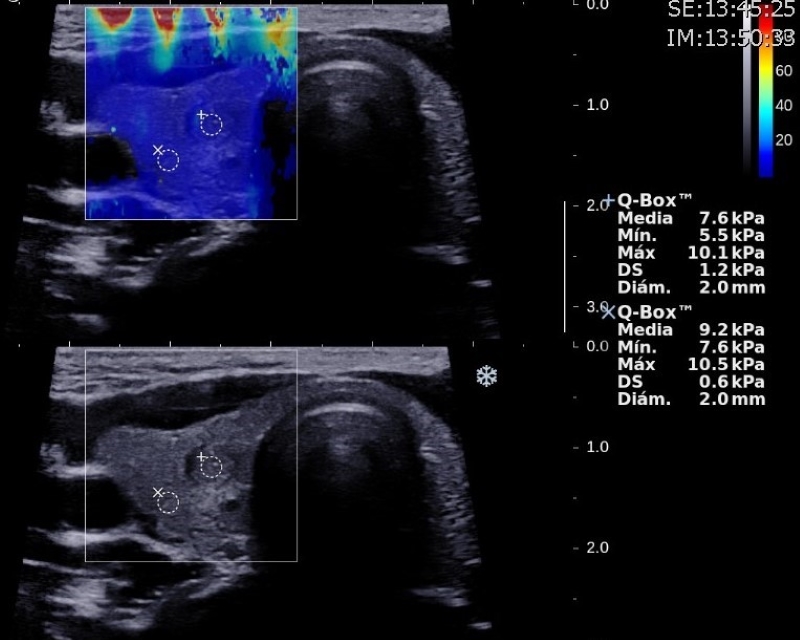

Dureza

La share wave elastography (SWE) es una nueva herramienta ecográfica que mide de manera cuantitativa la dureza o rigidez de un tejido, y reduce la subjetividad del diagnóstico clínico de la elasticidad de los nódulos. La SWE es efectiva para aumentar la sensibilidad de la ecografía en la detección de neoplasias tiroideas. Algunos autores definen al aumento de la elasticidad de un nódulo en relación con el parénquima tiroideo adyacente como mayor riesgo de malignidad. Hazem et al. establecen un valor medio para nódulos benignos de 33,46 ± 5,02 kPa y de 49,71 ± 11,16 kPa para nódulos malignos11,25. Las guías y recomendaciones de SWE publicadas por Ferraioli et al. en 2021 sugieren que los nódulos benignos muestran una elasticidad media de 15,3-28 kPa y que el punto de corte óptimo entre nódulos benignos y malignos es de 34,5-37,5 kPa26) (Figs. 21 y 22).